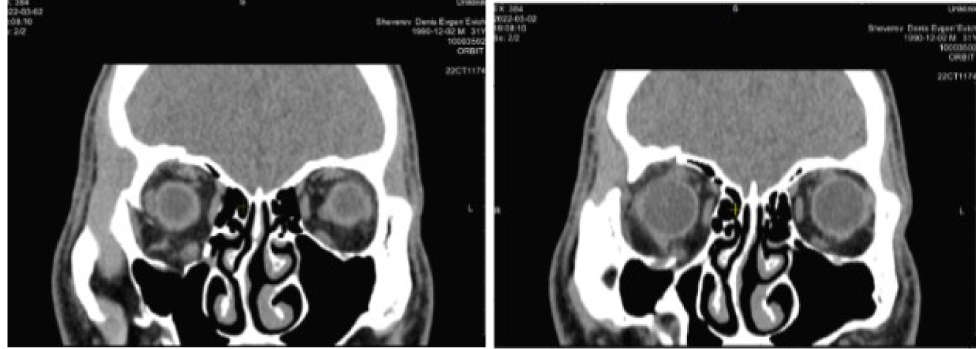

По результатам КТ и данным анамнеза на этапе планирования операции предположили отсутствие нижней прямой мышцы справа (рис. 6).

Рис. 6. Компьютерная томография орбит до операции. Клинический пример 2